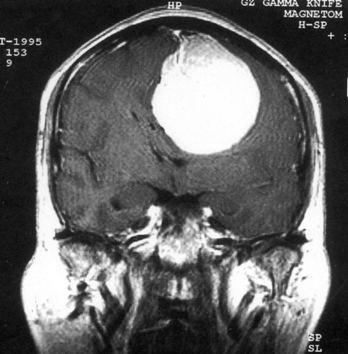

问题 病历摘要:??患者,男,40岁。发作性左下肢抽搐1年余,每次发作3~5分,每周发作1~2次。每次发作后感左下肢乏力,约半日后可自行恢复。既往身体健康。体检:神清,头顶部偏右有局限性骨性隆起(1.5×1.5cm),左鼻唇沟稍浅,伸舌居中。感觉、运动无明显异常。左浅反射减退,左下肢腱反射稍亢进,左Babinski征(-)。 下列对该患者的临床特点分析哪些是正确的?

选项 A.有Jackson癫痫发作 B.有Todd氏麻痹 C.有精神运动性癫痫发作 D.右中央前回可能有刺激性病灶存在 E.右中央后回可能有破坏性病灶存在 F.有失张力发作 G.右锥体束征(+) H.有颅内高压表现

答案 ABDG